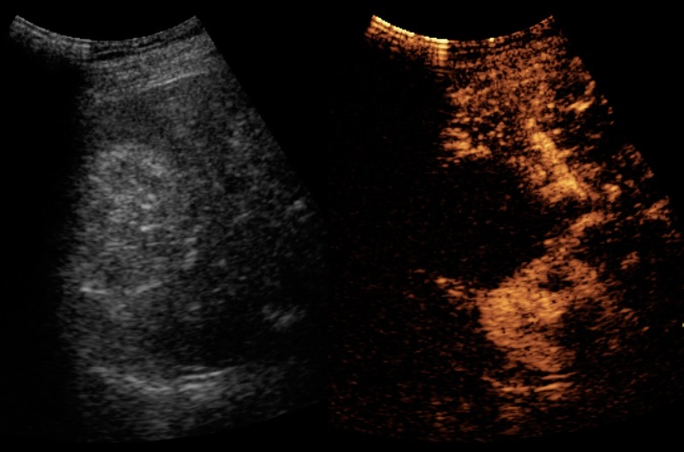

Ha eseguito negli anni oltre 20.000 esami ecografici (ecografie di primo e secondo livello, ecografie con

mezzo di contrasto (CEUS), procedure percutanee eco-guidate). Esperto in ecografia polmonare è stato tra i

ecografia diagnostica e interventistica di primo e secondo livello (diagnostica ecografica basale e

con mezzo di contrasto, esecuzione di procedure interventistiche ecoguidate quali la biopsia di

organi solidi o il posizionamento di drenaggi).